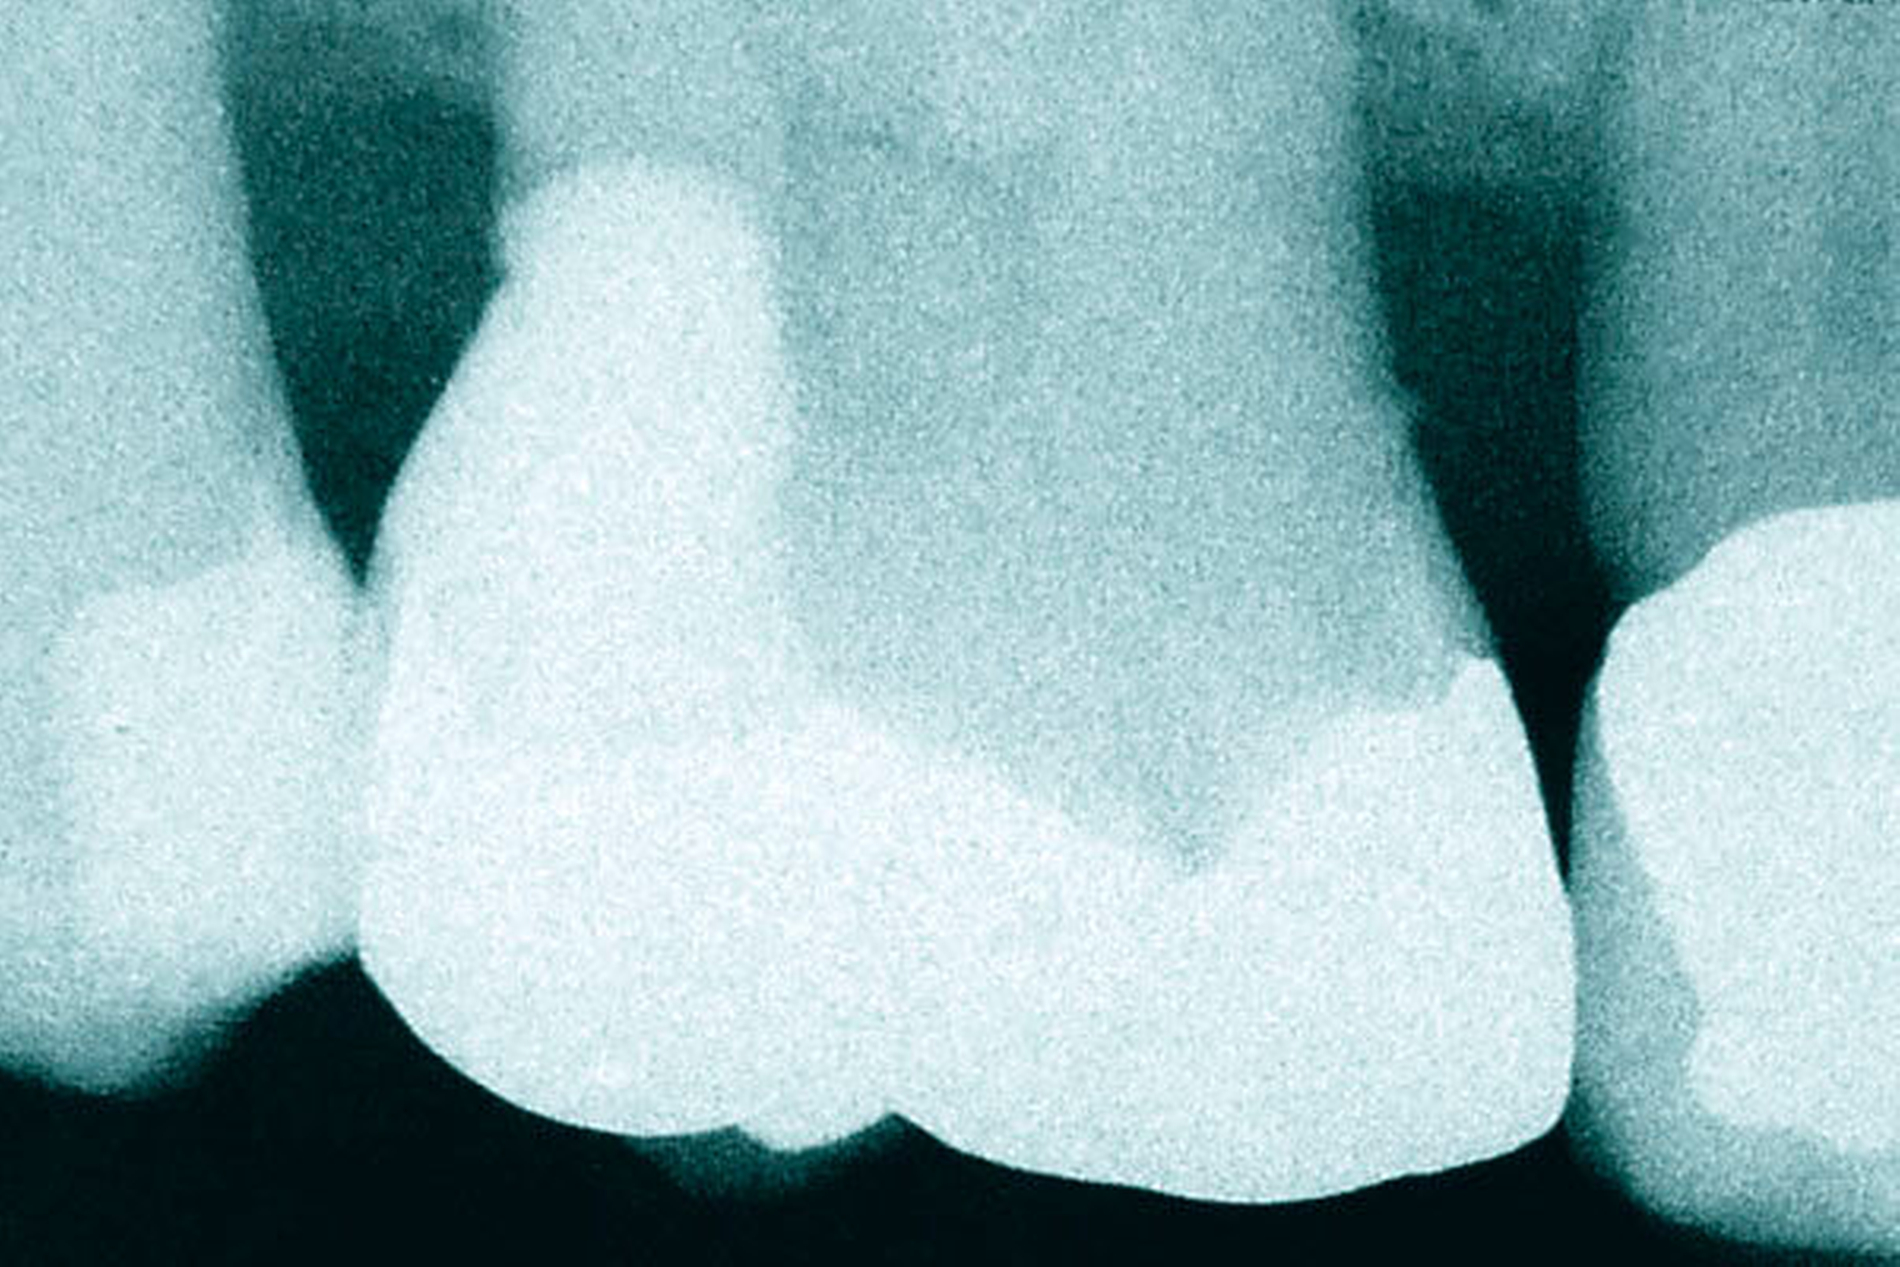

In den Abbildungen 1 bis 3 werden Optionen für frugale Interventionen auf restaurativem Sektor aufgeführt. Es handelt sich um direkte Vollüberkronungen im Frontzahnbereich (hier: hergestellt in R1-Technik / einphasig) (Abbildung 1), direkte Teilüberkronungen im Seitenzahnbereich (hier: hergestellt in R1-Technik / einphasig) (Abbildung 2), Reparatur-Restaurationen im Seitenzahnbereich (hier: hergestellt in R2-Technik / zweiphasig) (Abbildung 3). Technische Einzelheiten zur Vorgehensweise und den Ergebnissen sind an anderer Stelle beschrieben (Literatur siehe oben).

Für die in Abbildung 2 dargestellte Situation eines tief zerstörten Prämolaren gelten ähnliche Charakteristika. Es gibt in der restaurativen Zahnheilkunde viele Neuerungen, die das Behandlungsspektrum vergrößert haben. Dazu zählen unter anderem:

ein- oder zweiphasiges Vorgehen je nach Defektausdehnungen (R1- und R2-Technik),

von Präparationsgrenzen unabhängige Verschalungstechniken, die auch bei nicht-kariesbedingten Zahnhartsubstanzschäden (wie etwa Hypomineralisationen) zum Einsatz kommen können,

schadensgerechte Reparaturtechniken (Abbildung 3),

neuartige Insertionstechniken, die unter anderem die Anpassung neuer Restaurationen an vorhandene prothetische Versorgungen (Reziproktechnik) erlauben.